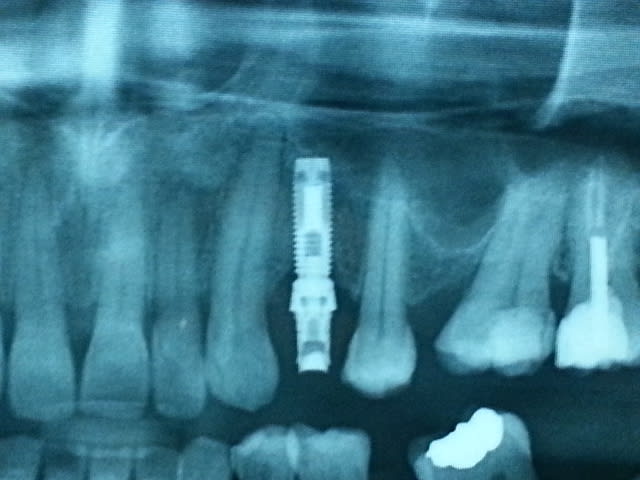

J'ai reçu un patient qui rapporte avoir poser ces implants il y'a 13 ans en Italie.

Selon vous, il s'agit de quel marque d'implant ?

Nobel mk1

je présume que c'est un hex externe, aurait tu une idée sur le diamètre de l’hexagone ou celui de la plate forme ?

oui, hex externe

je crois que c'est toujours la même plateforme...